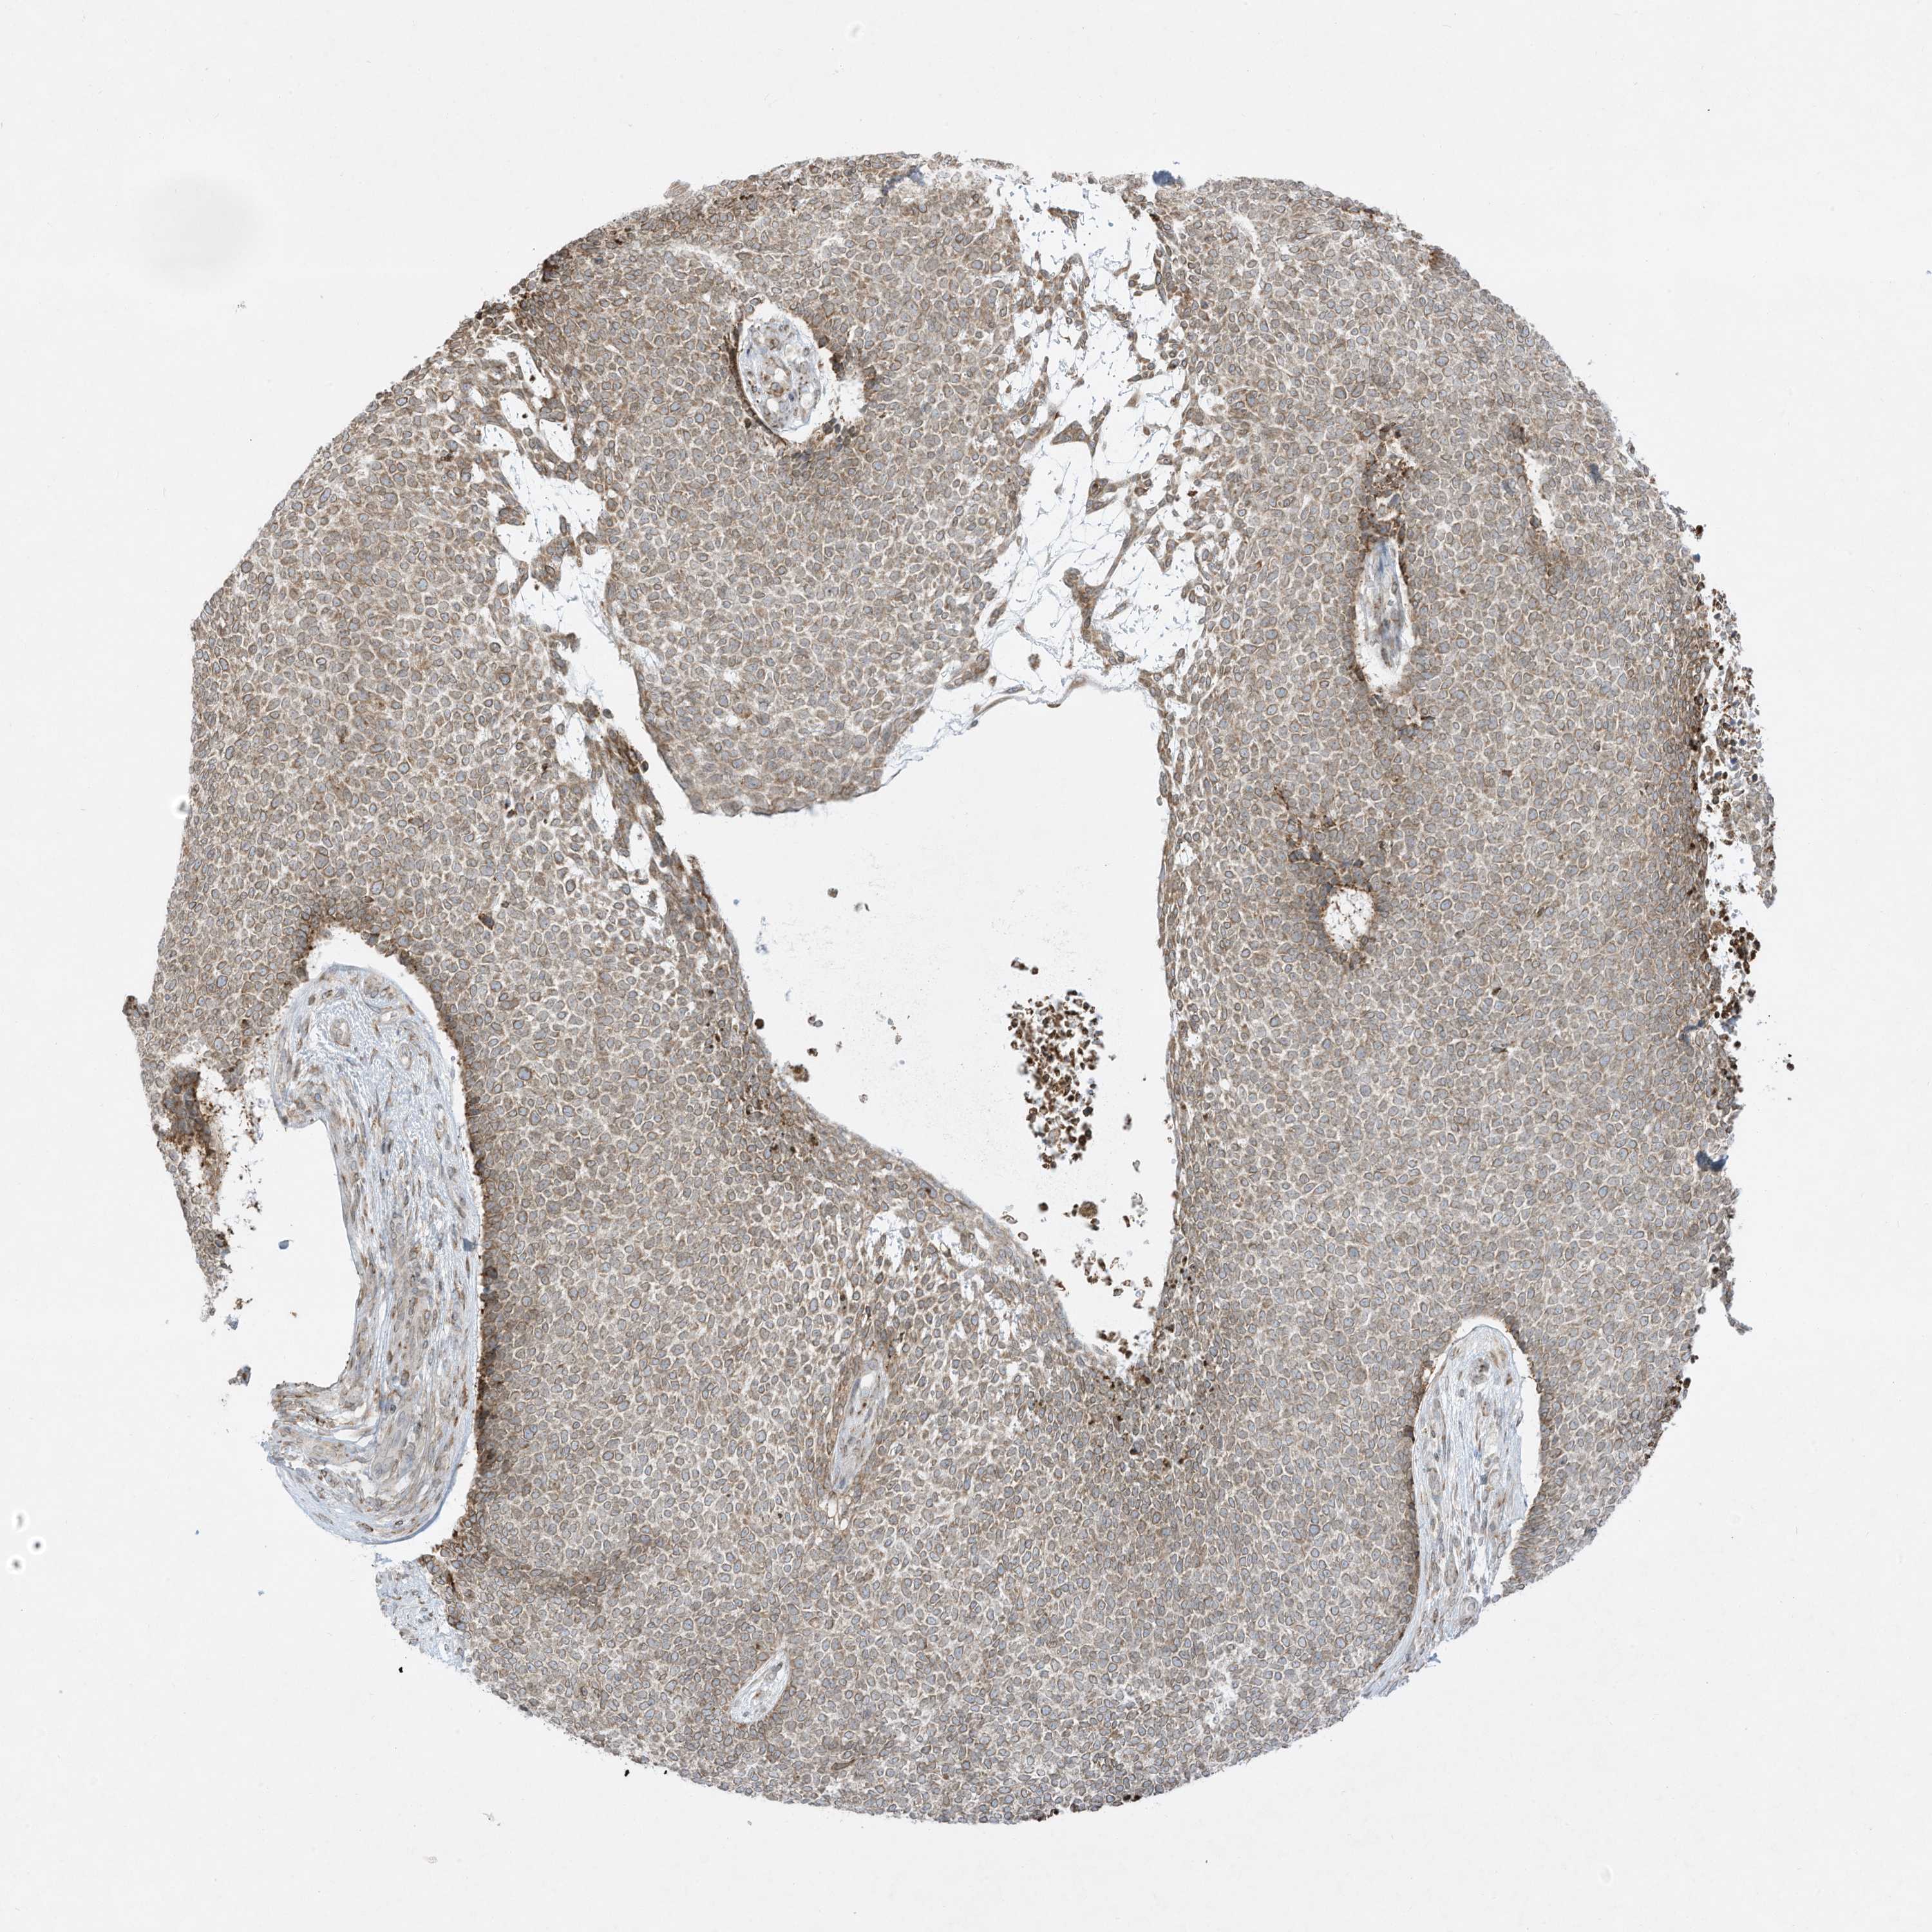

CANCER SKIN CANCER Show tissue menu

Basal cell and squamous cell cancer

SKIN CANCER - Protein expressioni

A mouse-over function shows sample information and annotation data. Click on an image to view it in a full screen mode. Samples can be filtered based on level of antibody staining by selecting one or several of the following categories: high, medium, low and not detected. The assay and annotation is described here.

Each image is clickable and will lead to virtual microscopy that enables deeper exploration of all samples and also displays staining intensity scores, fraction scores and subcellular localization as well as patient and tissue information for each sample.

Antibody HPA036071

Basal cell carcinoma

Squamous cell carcinoma, NOS

Squamous cell carcinoma, metastatic, NOS